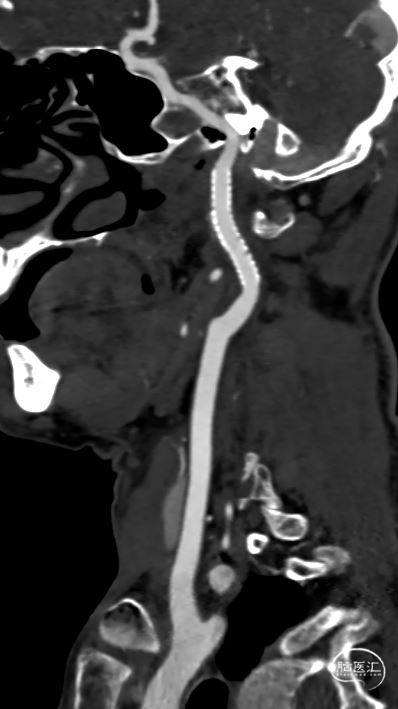

术后三个月随访:mRS 0分,颈部血管CTA显示支架形态良好。